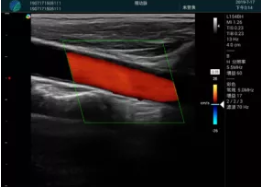

頸動脈血流充盈飽滿,無外溢

肝內(nèi)血管顯示清晰,血流敏感無外溢

2001年美國健康護理研究和質(zhì)量監(jiān)督局(AHRQ)批準了一項關于提高患者安全性的報告,建議:在頸內(nèi)靜脈中心置管術(shù)時使用超聲引導。此后超聲引導穿刺被用于幾乎所有的急診穿刺操作,尤其是血管穿刺。

便攜超聲在急診穿刺中的應用: